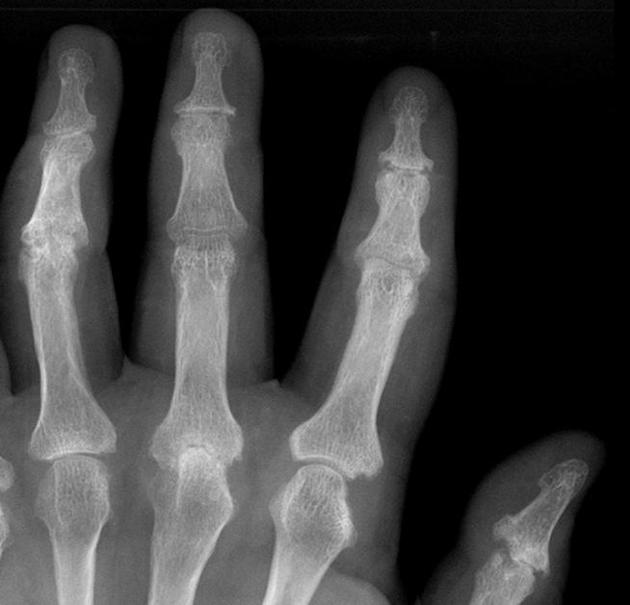

Diagnosis?

Imaging findings?

Psoriatic arthritis. Hands and feet most commonly involved. Rheumatoid factor negative, 60% HLA-B27 positive. Skin findings precede arthritis in 90%.

Periarticular marginal erosions and proliferation of bone (leads to “fuzzy” appearance). May see: pencil in cup deformity, sausage digit, “ivory phalynx-“

sclerotic distal phalanx of great toe, late- arthritis mutilans, asymmetrical sacroiliitis.